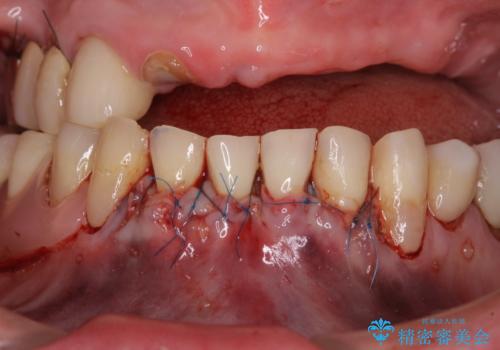

- 咬み合わせにより下の前歯の歯肉が退縮してしまい、根が見えていることが気になるとのことで来院された患者様です。

歯肉退縮に対して、上顎からの結合組織移植術(CTG)により、歯根の被覆を行うとともに、歯肉の厚みを増すことで将来の退縮リスクを抑制することとしました。

被覆量が不十分の場合には、追加で手術を行うことで患者様の了解を得ました。

歯肉が大変薄かったため、歯肉移植による根面被覆の効果はそれほど高くないように思われましたが、想像以上に歯肉の位置を回復させることができました。

歯肉の厚みも十分に獲得でき、患者様には大変満足していただきました。